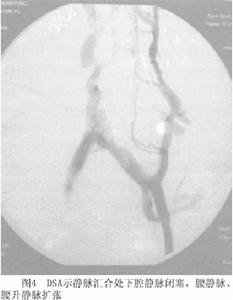

4.血管造影血管造影是明確BCS病變部位的最重要方法。一般可通過以下3種方法了解肝靜脈及下腔靜脈形態和血流動力學變化(圖3,4,5)。

(1)經股靜脈下腔靜脈插管:下腔靜脈完全性梗阻時,導管不能進入正常距離,向上逐漸出現阻抗測壓見下腔靜脈壓顯著升高;如果有下腔靜脈阻塞時,需同時經頸靜脈上腔靜脈插管作雙向造影可清晰顯示膜性結構的形態和阻塞距離的長短。此時,在阻塞部位以下可見附壁血栓,更可清晰顯示迂曲、擴張的腰靜脈、腰升靜脈脊柱前靜脈、膈靜脈及心包膈靜脈,亦可見血流經奇靜脈。可見一支或二支肝靜脈阻塞,阻塞下段擴張,或一支阻塞、另一支代償性擴張,亦可見各支肝靜脈間的分流。若沒有下腔靜脈阻塞操作嫻熟者導管不能進入靜脈,提示肝靜脈有梗阻。

(3)腹腔動脈和腸系膜上動脈造影及間接門靜脈造影:選擇性動脈造影也可明確診斷,此時常可顯示狹窄的伸直的肝動脈、高密度毛細血管影和門靜脈血液逆流。